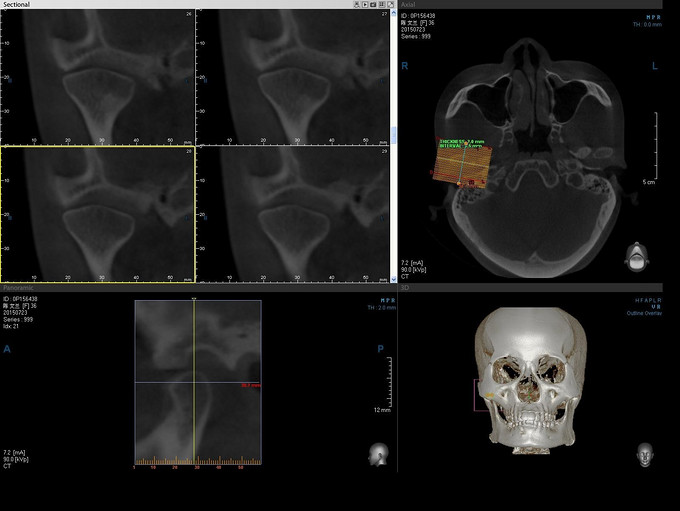

张口受限3年

双侧颜面部基本对称,双侧颞颌关节区无压痛,双侧髁突活动度减弱,开闭口未闻及明显弹响,开口度1.7cm,开口型偏左侧,下颌侧方运动受限。口内检查:口腔卫生状况一般,上下牙列咬合稳定,36、46残根。双侧面颈部未扪及明显肿大淋巴结

诊断:双侧颞颌关节紊乱综合征,局麻下行“双侧颞下颌关节灌洗术+关节盘松解复位术”,次日局麻下行“双侧咀嚼肌封闭治疗”。